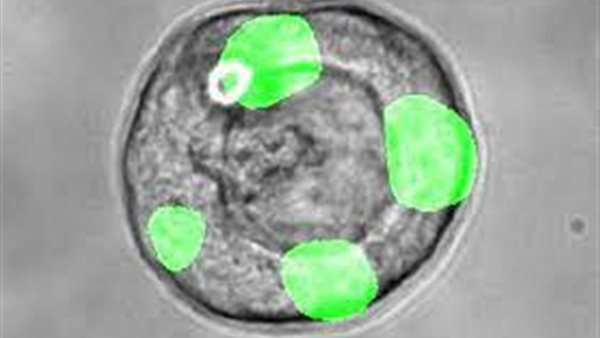

وحلل الباحثون بعدما نشروا النتائج، أنسجة الرئة البشرية لتحديد الخلايا الجديدة، والتي يسمونها الخلايا الإفرازية للمجرى التنفسي، وتعتمد الخلايا على فروع مجرى الهواء الصغيرة، عميقة في الرئتين، بالقرب من هياكل الحويصلات الهوائية حيث يتم تبادل الأكسجين لثاني أكسيد الكربون.

وأظهر العلماء أن هذه الخلايا لها خصائص شبيهة بالخلايا الجذعية تمكنها من تجديد الخلايا الأخرى الضرورية للعمل الطبيعي للحويصلات الهوائية.

ووفقًا للدراسة، كشف الباحثون عن أدلة على وجود الخلايا الجذعية السرطانية أثناء فحص إشارات النشاط الجيني لخلايا الرئة المأخوذة من متبرعين بشريين أصحاء.

وأدركوا أن الخلايا الجذعية السرطانية غير الموجودة في رئتي الفأر هي خلايا إفرازية، تتواجد بالقرب من الحويصلات الهوائية وتنتج البروتينات اللازمة لبطانة السوائل في مجرى الهواء.